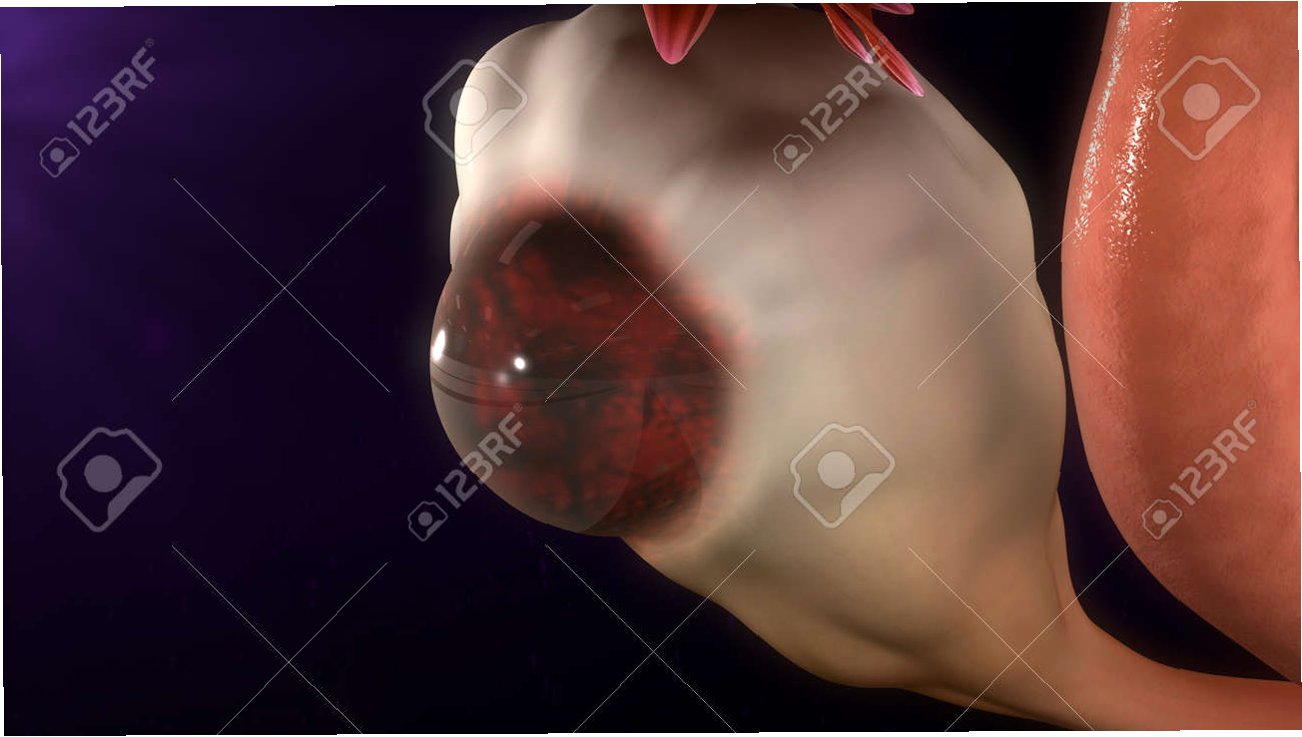

난소 낭종의 정의와 종류

난소 낭종은 난소에 물이 찬 혹이 생기는 증상으로, 난소는 여성의 배란과 호르몬 생성을 담당하는 중요한 기관입니다. 일반적으로 두 가지 종류의 난소 낭종이 있으며, 기능성 낭종은 난포가 제대로 성숙하지 못해 생기는 것이고, 난포성 낭종은 배란 후에도 난포가 남아 있을 때 발생합니다. 대부분의 경우 크기가 크지 않으면 자각 증상이 없지만, 일부는 복부 팽만감이나 통증을 유발할 수 있습니다.